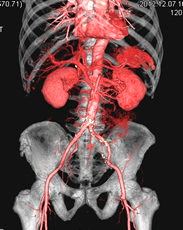

X線CT検査

X線装置を回転させることで、体内の断面像を画像として得ることができます。

造影剤という薬品を用いることで、血管や病変部を強調することもできます。

また、画像処理することにより、立体的な表示や血管部分のみを描出することもできます。

「診断部門」に320列CT装置と64列CT装置、救急外来に80列CT装置が稼働しています。